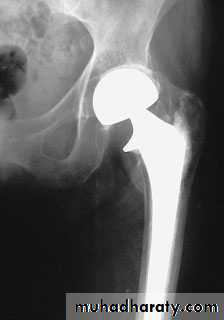

5.Austen Moore.6.Total hip replacement.